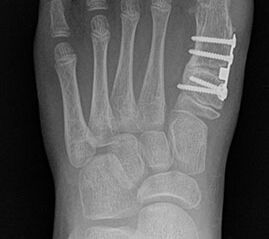

Röntgen

Standard ist die belastete Röntgenaufnahme des Fußes dorso-plantar und seitlich. Günstig ist eine Röhrenkippung von 10°-20°, um die Gelenke der Lisfranc-Linie einsehen zu können.

Bezüglich der Operationstechniken wird von früher häufig durchgeführten alleinigen Weich­teileingriffen am Großzehengrundgelenk aufgrund hoher Rezidivraten abgeraten 15. Die Operation nach Mc Bride mit lateralem Release, Exzision des lateralen Sesambeins, Abtragen der Pseudoexostose, Sehnenetransfer des M. adductor hallucis und mediale Kapselraffung zeigte unbefriedigende Mittel- und Langzeitergebnisse 16. Die Cerclage fibreux (mediale Kapselraffung) und das laterale Kapselrelease wird heute in Kombination mit einem knöchernen Eingriff angewendet. Bezüglich des Einsatzes von minimalinvasiven Operations­techniken vor Wachstumsabschluss liegen bisher keine Daten vor. Alle Osteotomien lassen sich nach Bedarf miteinander kombinieren. Es ist darauf zu achten, dass Osteotomien keine offenen Wachstumsfugen verletzen.

• Medial zuklappende Grundphalanxosteotomie nach Akin 17

• Subcapitale distale Chevron Osteotomie nach Austin 18

• Diaphysäre Osteotomie

• Scarf 19

• Ludloff 20

• Proximale Metatarsale I Osteotomien 21

• medial aufklappend – verlängernd

• lateral zuklappend – verkürzend

• bogenförmige Crescentic Osteotomie

• proximale Chevron Osteotomie

• proximale Verschiebeosteotomie

• medial aufklappende Cuneiforme I Osteotomie 1522

• Wachstumslenkung: Hemiepiphysiodese der lateralen Basisfuge am Metatarsale I  23

• Nach Schluss der Wachstumsfugen: TMT I Arthrodese nach Lapidus 2425